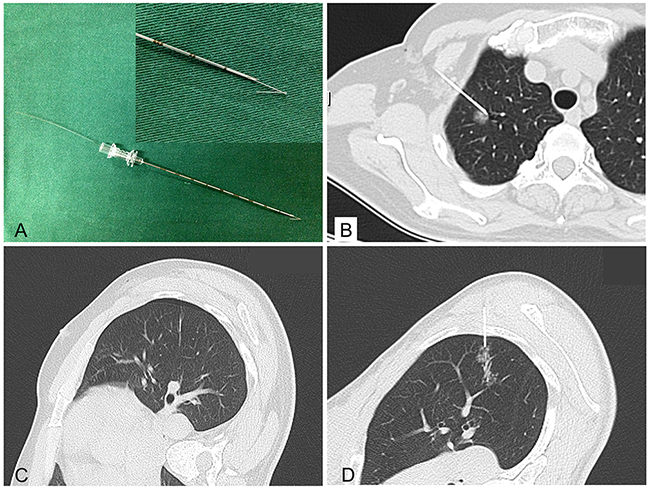

Hookwire localization under CT guidance

Hookwire localization was performed on the day of surgery just before VATS. Patients were taken to the radiology unit and placed on the CT scan table in a prone, supine, or lateral decubitus position, depending on the location of the lesion. A calibrated cannula (21-gauge, 10 cm long) and a 20-cm long calibrated wire with a thorn constituted the Hookwire system (Pajunk GmbH Medizintechnologie, Geisingen, Germany; Figure 2A). The procedure were performed by one of four experienced chest interventional radiologists (X.H.H., G.D.L., L.C.X., Y.H.W.) who had 5–10 years of experience performing Hookwire localization. All procedure were performed under non-enhanced CT guidance with a low-dose technique (64×1.25 mm detector configuration, pitch of 1.4, table speed of 28 mm/rotation, 0.5 second gantry rotation, helical mode, 120 kVp localizing/100 kVp subsequent guiding scans with 40–60 mA) using a 64-detector–row CT scanner (SOMATOM Sensation 64, Siemens Medical Solutions, Forchheim, Germany). First, thorax CT scan (planning procedure) was performed to identify the location, size of the pulmonary lesion, as well as the relationship with the surrounding tissues. An optimal route was designed to traverse the shortest transpulmonary distance and avoid vital intrathoracic structures. After local anaesthesia, the cannula needle with Hookwire was inserted gradually through the chest wall into pulmonary parenchyma and placed as close as possible to the lesion (Figure 2B) under sequential CT guidance. Selected images were acquired in the area of interest with 3-mm-thick contiguous transverse CT sections (guiding procedure). Once optimal placement of the localizing needle tip was confirmed by CT, the outer cannula needle was withdrawn and the horn of Hookwire was placed adjacent to the target nodule. The patient was quietly breathing when the wire was placed. Repeated CT scan (control procedure) was performed to confirm whether the horn anchored the target lesion and evaluate associated complications including pneumothorax (Figure 2C), hemorrhage (Figure 2D) and so on. During the procedure, blood pressure, breathing rate and arterial oxygen saturation of patients were monitored. The Hookwire outside the chest wall was positioned carefully on the skin under sterile gauze. The patient was then transferred to operating room directly for VATS. In the meanwhile, images reconstructed by radiologists were uploaded to Picture Archiving and Communication System for thoracic surgeons to consult. Location time was defined as the duration time from first CT scan for identify the location to last CT scan for verify placement of the localizing Hookwire. Successful localization was defined as inserting Hookwire into the lesion or its surrounding 10mm range without obvious migration or dislodgement before VATS. The time of transferring to operating room was defined as time interval between CT unite and operating room.

Figure 2: Hookwire system and the relative complications of localization. (A) Hookwire system (Pajunk GmbH Medizintechnologie, Germany); (B) Hookwire has anchored the lesion; (C&D) Minimal pneumothorax and needle track hemorrhage.